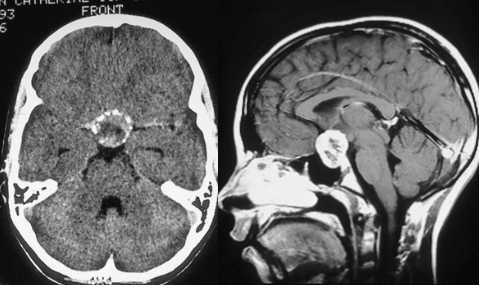

“这个肿瘤可不好切,”面对医生的摇头叹息,安达父母再一次陷入绝望,“你们看,孩子的肿瘤位置很深,现在已经对视神经产生压迫了,所以孩子才会出现视力下降。你们想要全切除,手术难度太大了,弄不好会失明,而且术后还可能导致终生的内分泌功能障碍, 严重影响生活质量。”

不幸的是,安达到了12岁时,已经开始出现视力下降的问题,再不手术,安达很有可能逐渐失明,父母明白,此时的形势已经无法再等下去了。

鲁特卡教授很快对安达的病情进行全面分析,最终确定了一个手术方案,在与安达家人进行沟通并取得同意后,一场承载着一个小女孩未来的手术正式开始了。